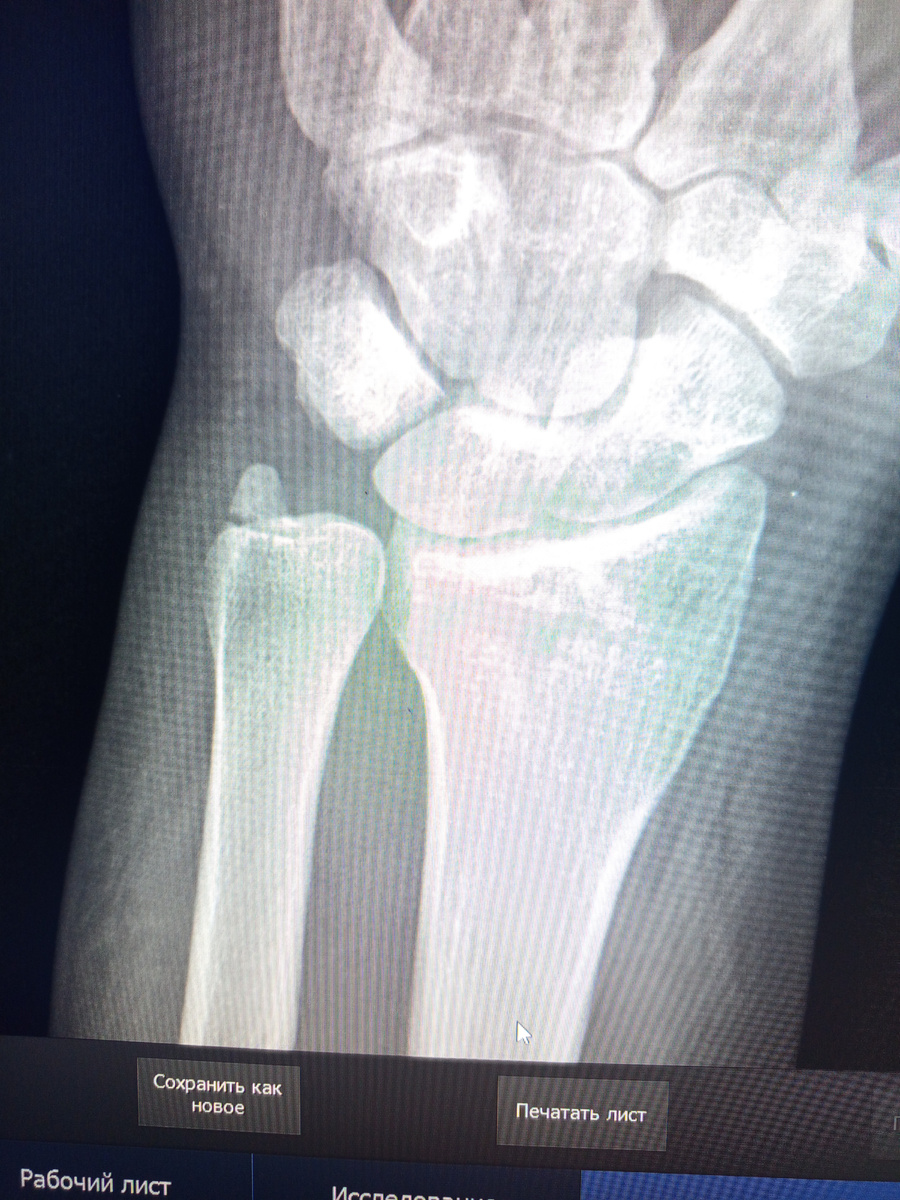

Заходит парень , 20 лет. Назначили снимок лучезапястного сустава.

Рука чуть припухла.

Нормально, на гипс потянет. Хорошо отпраздновал.